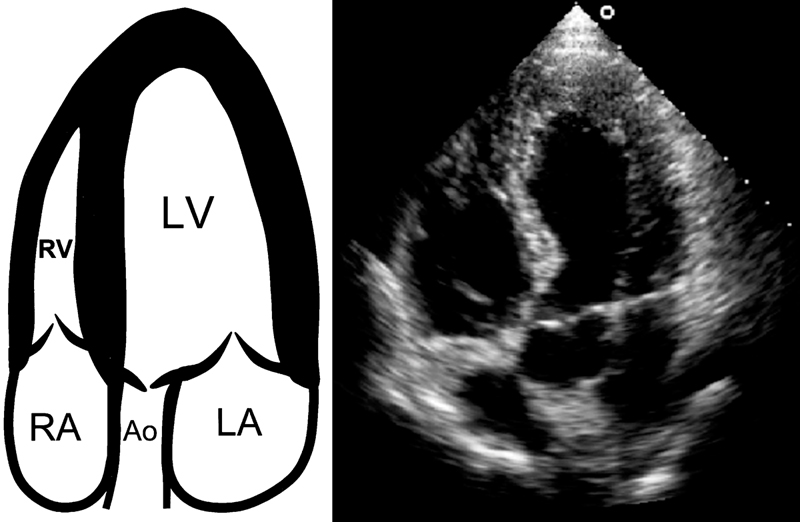

فحوصات تشخيصية لبعض امراض القلب والشرايين التاجية